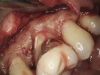

(4.) The granulation tissue was removed in its entirety, and the defects were treated with a 90% TCA solution.

Figure 4

(5.) The defects were filled with a bioactive, biocompatible calcium silicate-based restorative cement.

Figure 5

(6.) Immediate postoperative view after the flap was sutured into place (Photography courtesy of Stephen Fucini, DMD).

Figure 6